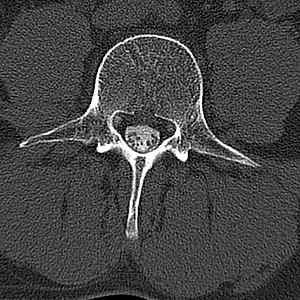

Hierzu wird eine Computertomographie des betreffenden Wirbelsäulenabschnittes durchgeführt, wobei in der Kontrastierung des Nervenwasserraumes eine im Vergleich zur herkömmlichen (d.h. nicht kontrastmittelverstärkten) Computertomographie wesentliche Zusatzinformation liegt. Beispielsweise können die Auswirkungen knöcherner degenerativer Veränderungen (Einengungen) auf die Nervenwurzeln exakt dargestellt werden.